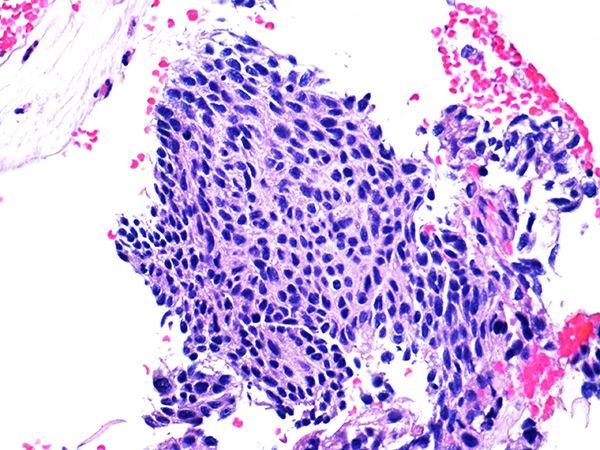

Case 2

Soft Bx CIN 2

40x - High Power